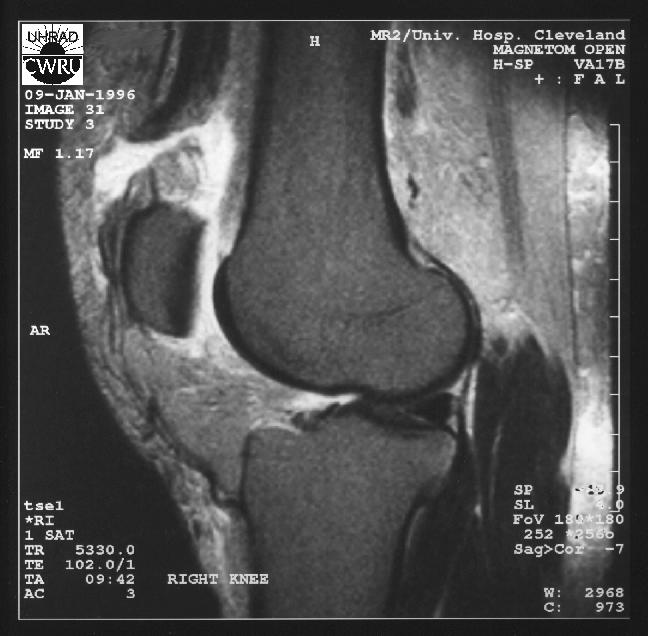

From radiologyspirit.blogspot.com

RadiologySpirit Quadriceps Tendon Tear, Quadriceps Muscle Tear Diagnosis Quadriceps strains occur when one of the muscles in the front of the thigh stretches or breaks, often due to physical activities such. Diagnosing a quadriceps tendon tear. Most can be diagnosed by a. A complete tear of the quadriceps tendon is a disabling injury. The quadriceps tendon is derived from the muscular junction of the rectus femoris, vastus lateralis,. Quadriceps Muscle Tear Diagnosis.